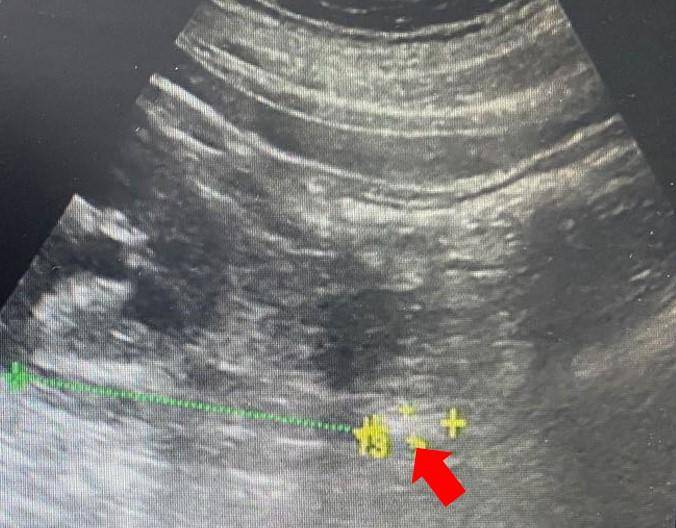

(左图:肾积水,红色箭头标注的部分就是肾积水,肾窦分离大概10mm;右图:箭头所标注是输尿管上段内的结石,大小大概17x7mm)

我们在实际工作当中,一部分患者可以清楚的扫查到输尿管结石,从而观察结石的大小,位置;而另一部分患者,由于肠腔气体的遮挡,并不能直接观察到结石,只能看到肾脏及输尿管的积水。